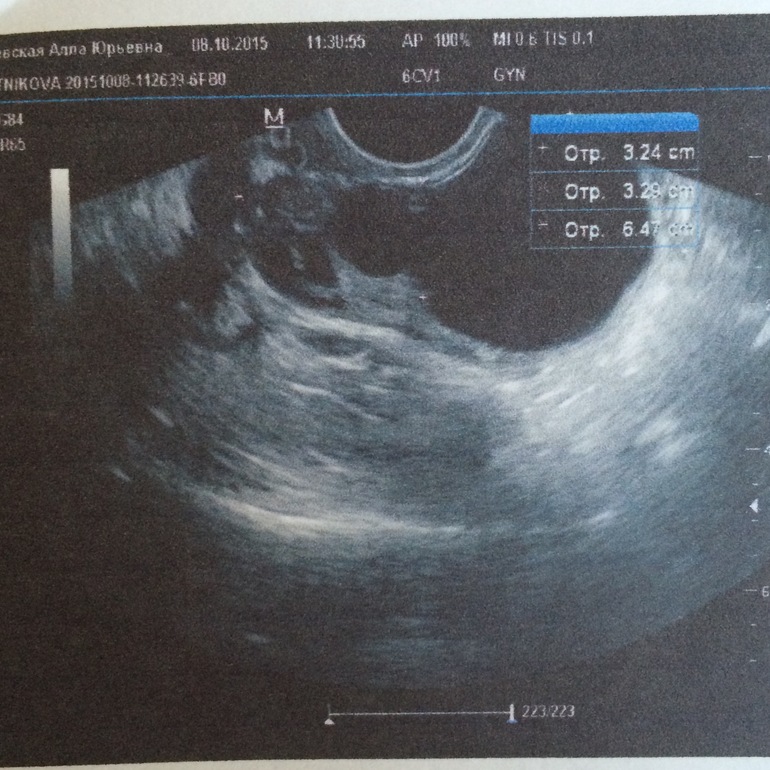

Была сегодня на Узи думала после капельниц с магнезией киста выйдет с М, но нет она все ещё во мне сегодня начну пить регулон, но почему такой огромный левый яичник?фото Узи подкат

огромная киста и я бы еще на эндик обратила внимания для 3 дц он очень большой. у вас что эндометрий при м не оттаргается?

Огромная киста это см 8)) 3 см это не так уж страшно.

забыла написать месяц назад объем яичника был 50мм при такой же кисте,а в этом цикле сразу на 2 см увеличился вот я и заволновалась.

За счет кисты увеличен яичник. На регулоне думаю за месяц все уйдет

Надеюсь регулон поможет справится с кистой сказали что она фолликулярная